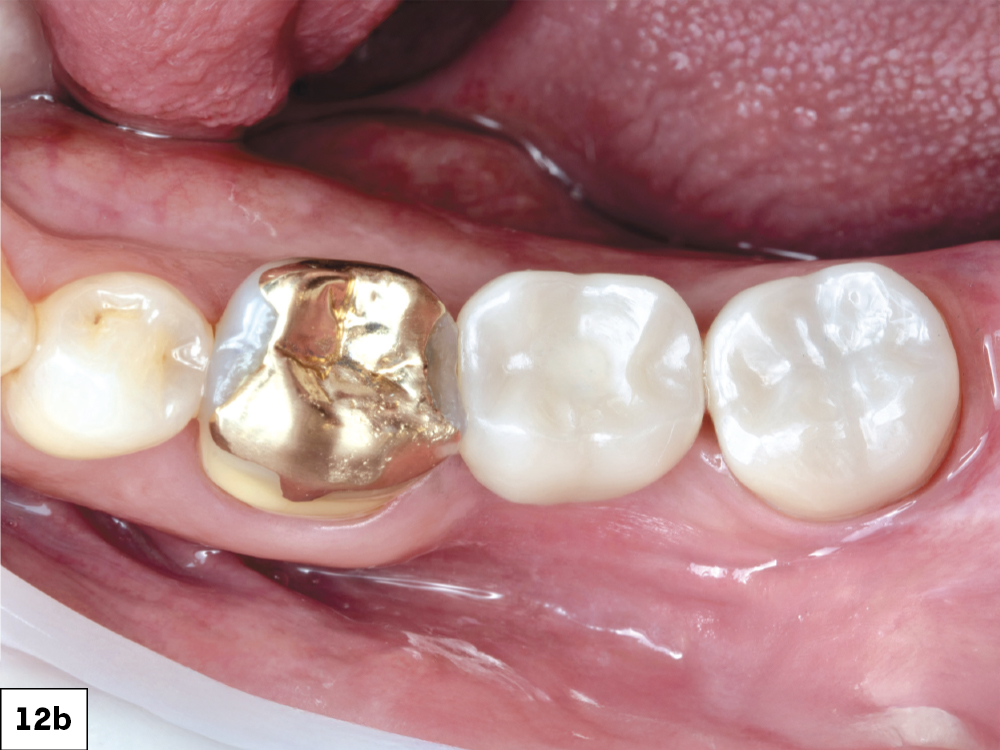

In-office milling is a quickly evolving option for the modern dental practice. With the introduction of a same-day screw-retained option, BruxZir® NOW SRC milling blocks, there’s even more opportunity for optimizing single-unit restoration workflows. In this case study, I’ll demonstrate how this product can be used as part of an efficient workflow for tooth replacement in the posterior. When combined with guided surgery and in-office crown design, this procedure offers reliable results while saving money and significantly cutting down on chair time for dentists.